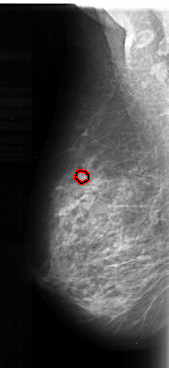

A_1097_1.LEFT_MLO

LEFT_MLO LINES 5506 PIXELS_PER_LINE 2521 BITS_PER_PIXEL 16 RESOLUTION 42 OVERLAY

FILE: A_1097_1.LEFT_MLO.OVERLAY

TOTAL_ABNORMALITIES 1

ABNORMALITY 1

LESION_TYPE CALCIFICATION TYPE PLEOMORPHIC DISTRIBUTION CLUSTERED

ASSESSMENT 4

SUBTLETY 4

PATHOLOGY MALIGNANT

TOTAL_OUTLINES 1

BOUNDARY